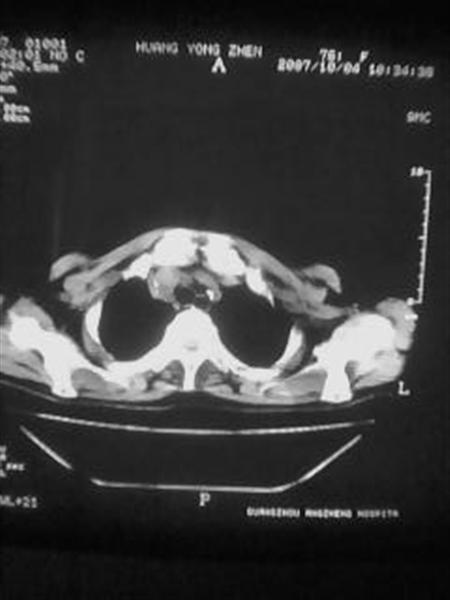

标题: CT10080:F76Y,各位老师发表高见!!! [打印本页]

标题: CT10080:F76Y,各位老师发表高见!!!

右下肺周围型肺癌伴双肺右侧叶间 胸膜及右肺门淋巴结转移

考虑:肺癌伴肺、胸膜 纵隔淋巴结转移可能性大!